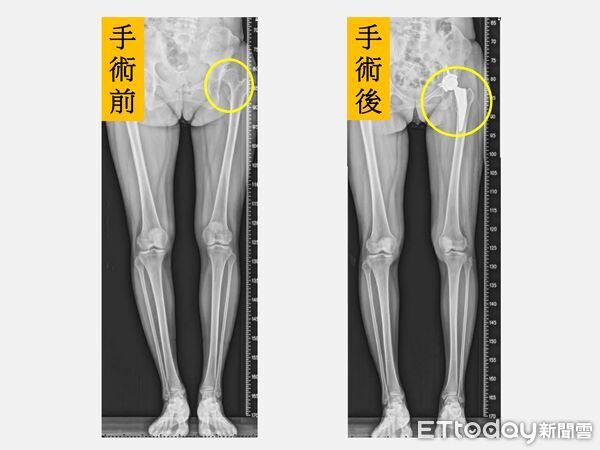

▲左邊髖關節進行「微創正前開髖關節置換手術」後(右圖圓圈處),2隻腳一樣長(圖/記者游瓊華翻攝)

手術當天下午,麻醉藥效一退,陳小姐即在醫療團隊陪同下嘗試踩固定式腳踏車。她形容,原本以為會痛,結果卻幾乎沒有疼痛感,「兩隻腳突然一樣長,腳踩在地上的感覺很不真實,好像睡了一覺醒來,人生被重新校正。」那一刻,她忍不住紅了眼眶。